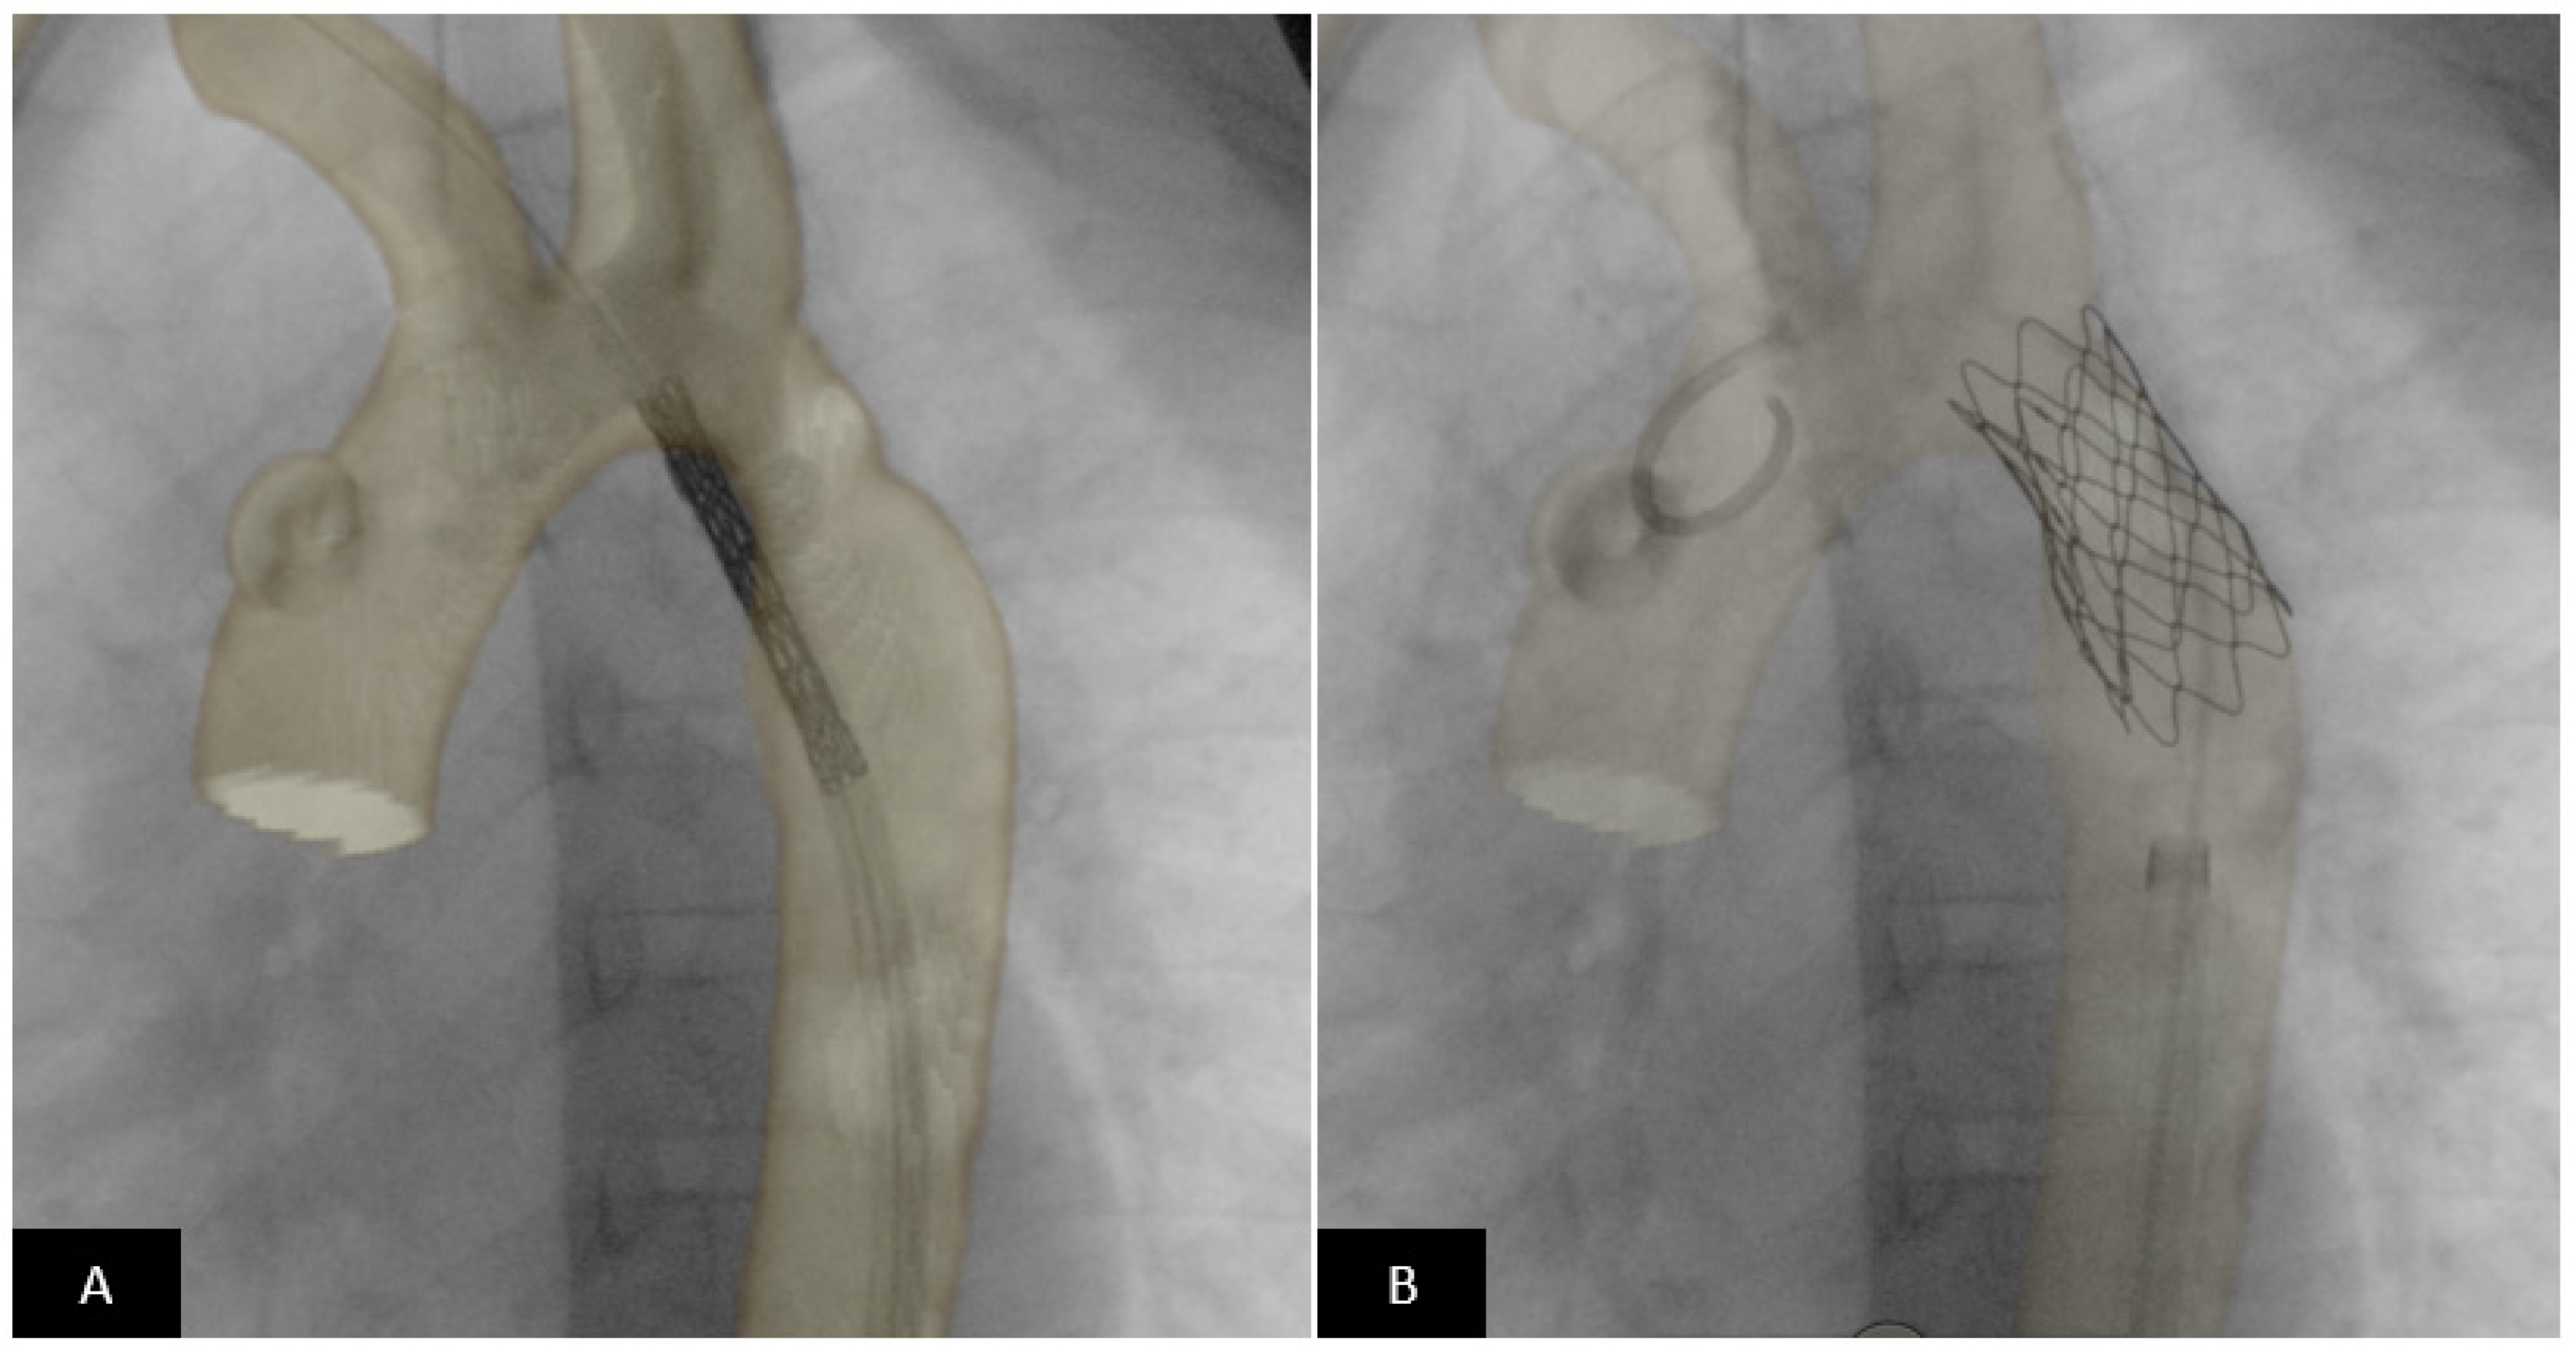

- Valverde, I.; Gomez, G.; Coserria, J.F.; Suarez-Mejias, C.; Uribe, S.; Sotelo, J.; Velasco, M.N.; Santos De Soto, J.; Hosseinpour, A.R.; Gomez-Cia, T. 3D printed models for planning endovascular stenting in transverse aortic arch hypoplasia. Catheter. Cardiovasc. Interv. 2015, 85, 1006–1012. [Google Scholar] [CrossRef] [PubMed]

- Pluchinotta, F.R.; Sturla, F.; Caimi, A.; Giugno, L.; Chessa, M.; Giamberti, A.; Votta, E.; Redaelli, A.; Carminati, M. 3-Dimensional personalized planning for transcatheter pulmonary valve implantation in a dysfunctional right ventricular outflow tract. Int. J. Cardiol. 2020, 309, 33–39. [Google Scholar] [CrossRef]